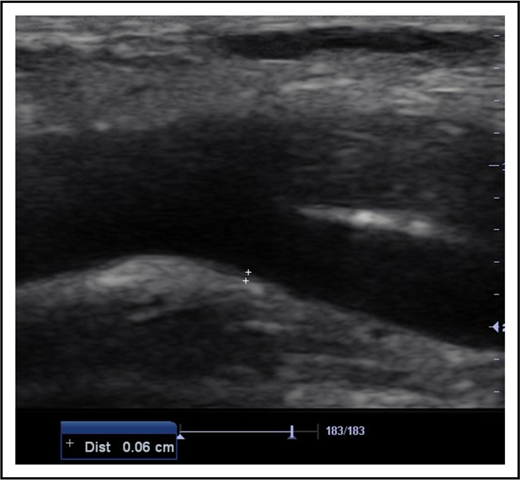

All subjects were examined in the supine position. Deep venous thrombosis of the femoral, popliteal, and calf veins was ruled out in each of the 154 limbs of the participants (88 limbs of SCD subjects and 66 limbs of controls) using compressibility test and venous distension on performance of Valsalva maneuver during B-mode ultrasonography.13 This was done to exclude the possibility of a venous ulcer. Thereafter, the CFAs were scanned in the longitudinal plane. Frozen B-mode images of 3 separate measurements of each CFA IMT were captured in end-diastole at a position on the far wall of the artery where it bifurcated into the femoral and deep femoral arteries (Figure 1). This point was chosen because IMT is most common at points of bifurcation in SCD patients.6 IMT was defined as the distance from the leading edge of the lumen-intima interface to the leading edge of the media-adventitia interface of the far arterial wall. The mean IMT from the 3 separate measurements for each CFA was calculated.14

B-mode longitudinal axis image of the CFA at its point of bifurcation. The measurement point on its far wall for IMT is denoted by the cursors (6 mm in this patient). Dist, distance.